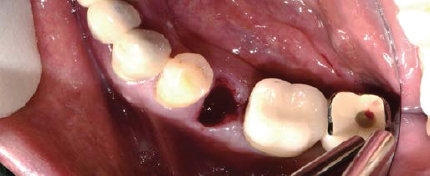

술전

발치

발치와